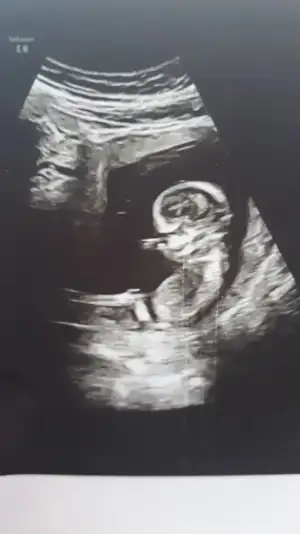

7+2 haftalık ve vajinal ultrason..

Eki Görüntüle 2777351 Eki Görüntüle 2777352

Kız sanki 11 12 13 haftalar olmalıBuda benim bebişim. Tahminde bulunabilen varsa sevinrm. İçime hep erkek doğuyor.

Kız sanki emin olamadım 13 hafta USG olursa paylaşınEki Görüntüle 2777828 11+5 tahminlerinizi alabilirsek çok seviniriz, çok merak ediyoruz![]()

14 +0 hafta hanımefendi. Doğru pozisyona tam gelmedi baya kıpır kıpırdı hep döndü durdu. en alınabilir görüntü bunlar malesef. bi dahakine zaten öğrenmiş olurum heralde. yinede saolun.Kız sanki emin olamadım 13 hafta USG olursa paylaşın